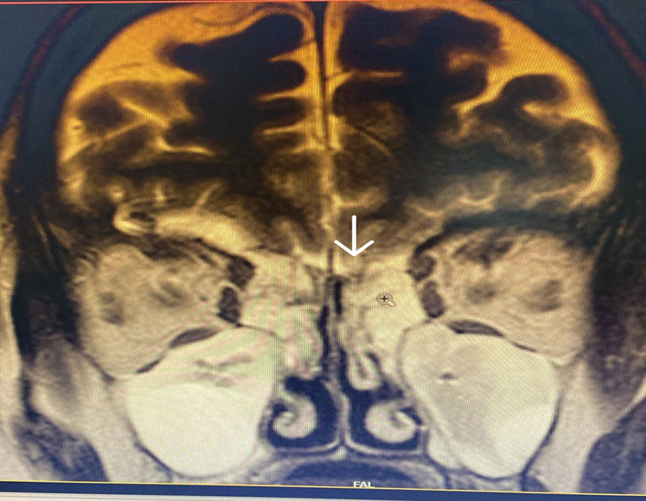

MRI brain with anterior skull base revealed protrusion of the anteromedial left temporal lobe in to the left sphenoid sinus which was hyperintense on T2 and normal on T1 and FLAIR sequences suggestive of encephalocele (figure 3). The left gyrus rectus shows inferior elongation with no definite encephalocele at the cribriform site (figure 3A).

Figure 3. MRI brain with skull base –normal signal on T1 and FLAIR with hyperintense on T2 signifying protrusion of the anteromedial temporal lobe with left meningoencephalocele.